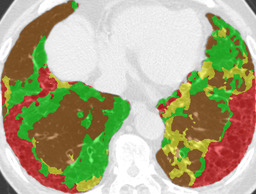

Recall, precision, and dice coefficient (a.k.a F-measure) were used for the evaluation. For the sake of the evaluation, continuous softmax outputs were converted into discrete class labels by selecting the classes that gave the maximum probability. Table 2 shows the evaluated metrics for each method. By paired t-tests, statistically significant differences were confirmed between the proposed method (λ=0.1𝜆0.1\lambda=0.1) and other methods in dice coefficients. As shown in Table 2, utilizing weakly annotated pixels increased precision and λ=0.1𝜆0.1\lambda=0.1 was the optimal value that balances recall and precision in this experiment. Evaluated dice coefficients for the proposed method (λ=0.1𝜆0.1\lambda=0.1) are shown in Figure 2. As shown in Figure 2, even though the proposed method improved the segmentation accuracy, segmentation accuracy varies between slices. Figure 3 shows the confusion matrix of the pixel-wise classification result. In Figure 3, Lweaksubscript𝐿𝑤𝑒𝑎𝑘L_{weak} pixels misclassified as corresponding Lstrongsubscript𝐿𝑠𝑡𝑟𝑜𝑛𝑔L_{strong} (e.g. pixels of lCON¯subscript𝑙¯𝐶𝑂𝑁l_{\overline{CON}} classified as lCONsubscript𝑙𝐶𝑂𝑁l_{CON}) are represented as “Others”. As shown in Figure 3, DLD class combinations with similar texture patterns such as HCM and EMP were misclassified into each other. Figure 4 shows the average result for each DLD class and tested method.

Ground truth Supervised only Proposed (λ=0.1𝜆0.1\lambda=0.1) Proposed (λ=1𝜆1\lambda=1)

CON \blacksquare

Refer to caption Refer to caption Refer to caption Refer to caption

0.839 0.868 0.824

GGO \blacksquare

0.693 0.676 0.876

HCM \blacksquare

0.581 0.770 0.435

EMP \blacksquare

0.793 0.847 0.815

NOR \blacksquare

0.978 0.968 0.974

Figure 4: Average results and dice coefficients for each DLD pattern. Automated segmentation results are superimposed with colors. For each DLD pattern, the slice that gave the median dice coefficient for the proposed method with λ=0.1𝜆0.1\lambda=0.1 was chosen to represent the average result. Note that although CNN performed multi-class segmentation, only one DLD pattern per slice was taken into account for the evaluation.